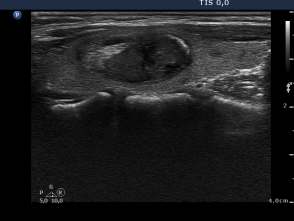

Third session of sclerotherapy (fourth row of images):

The lesion decreased in size. After removal of 2 mL bloody fluid we injected 4 mL ethanol.